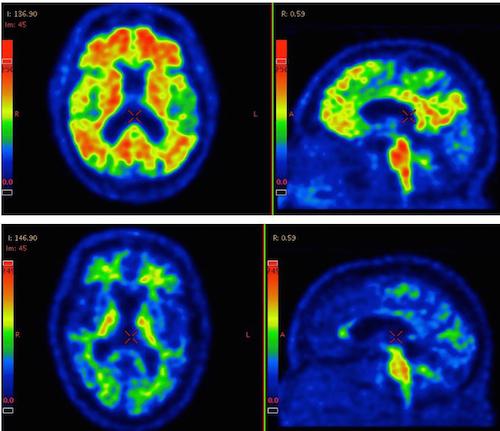

*Photo PET MRI Feature: The illuminated areas (red, yellow and green) indicate an accumulation of the protein beta-amyloid. The top row shows a patient diagnosed with Alzheimer's disease's brain. Bottom row shows the brain of a healthy person. There is always an unspecified binding of the colour marker, which explains the illuminated spots in the healthy brain. Photo: Swedish Biofinder Study

However, further studies are needed to verify the results. Apart from the number of participants, the strengths of this study include the use of three different methods to achieve acurate measurement results: cerebrospinal fluid samples, the use of a so-called PET scanner, and genetic analysis. A weakness of the study is that it does not include any measured observations of the brain tissue, which is often the case in studies of Alzheimer's disease.